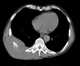

Chest mass

A chest radiograph, called a chest X-ray (CXR), or chest film, is a projection radiograph of the chest used to diagnose conditions affecting the chest, its contents, and nearby structures. Chest radiographs are the most common film taken in medicine. [Source: Wikipedia ]